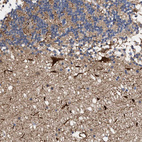

Immunohistochemistry analysis in human cerebral cortex and pancreas tissues using HPA003282 antibody. Corresponding ALDOC RNA-seq data are presented for the same tissues.